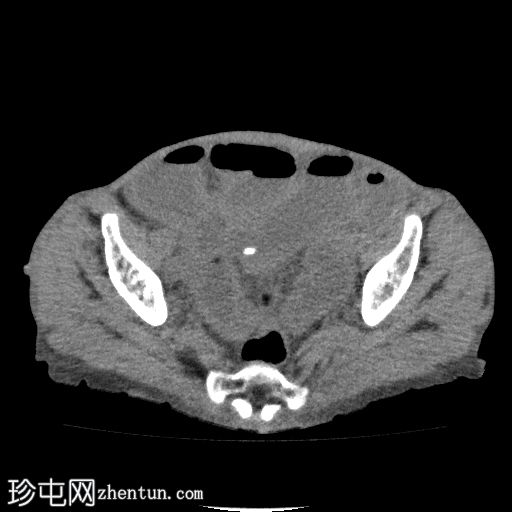

轴位

平扫

回肠肠袢套入盲肠,形成肠套叠形态,轴位和纵位图像分别可见靶征和腊肠征或假肾征。